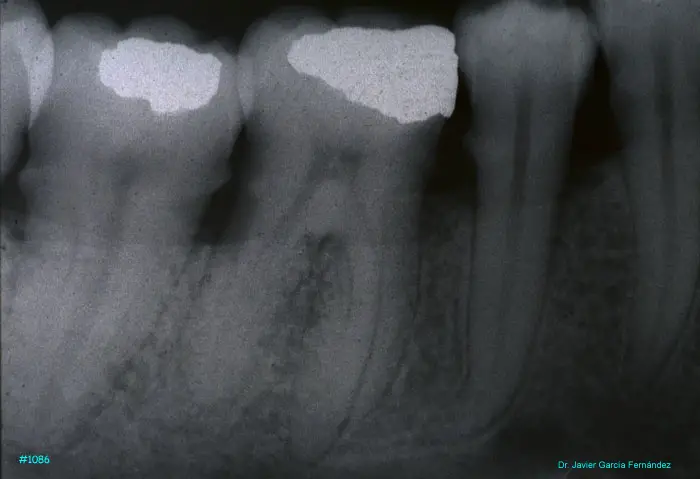

Atlas of Surgical Techniques in Periodontics. Chapter III. Atlas de Técnicas Quirúrgicas en Periodoncia

image455